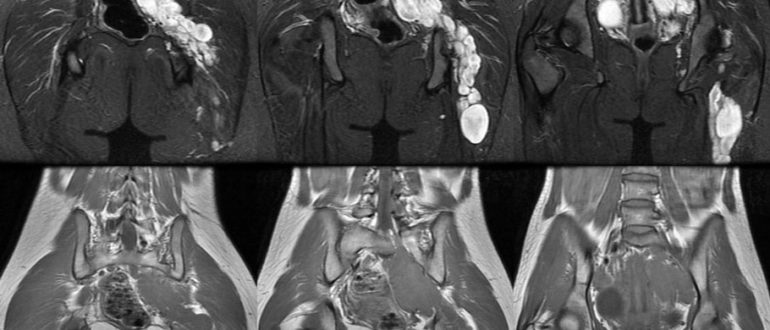

МРТ дермоидной кисты

Дермоидная киста: симптомы и причины, диагностика, лечение и профилактика Дермоидная киста – это полое доброкачественное образование, представляющее собой плотную капсулу, с содержимым из частичек дермы, волос, сальных элементов….